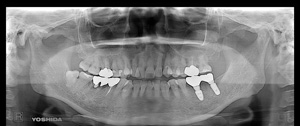

@@R.S‚³‚ñ@56Î —«  ‘åŠw‹³Žö @Žèp“ú@‚Q‚O‚O‚W”N ‚QŒŽ ‚X“úi“yj@㉺Š{  ƒm[ƒxƒ‹ƒKƒCƒhŽg—p@Ö¬“à’ÁÖ@•¹—p@@@

@@@@@ãŠ{  All on ‚U@‘¦Žž‰Ád@@

@@@@@@@@@@@@@ Rpl Tapered Rp  ‚P‚O mm(‚U–{)

@@@@@‰ºŠ{¶‰E@‘¦Žž‰Ád@ ‚R Unit Bridge@

@@@@@@@@@@@ @Rpl Tapered Rp  ‚P‚O mm(‚S–{)@@–ƒWƒ‹ƒRƒjƒAƒNƒ‰ƒEƒ“‚ÅÅI•â’Ô